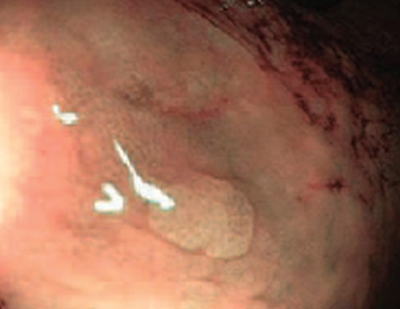

1 тип — характерний для гіперпластичного поліпа

Судини: світліші або схожі на навколишні

Поверхня: круговий візерунок з дрібними крапками — візерунок із темнішою ділянкою в центрі, оточений світлішою слизовою оболонкою